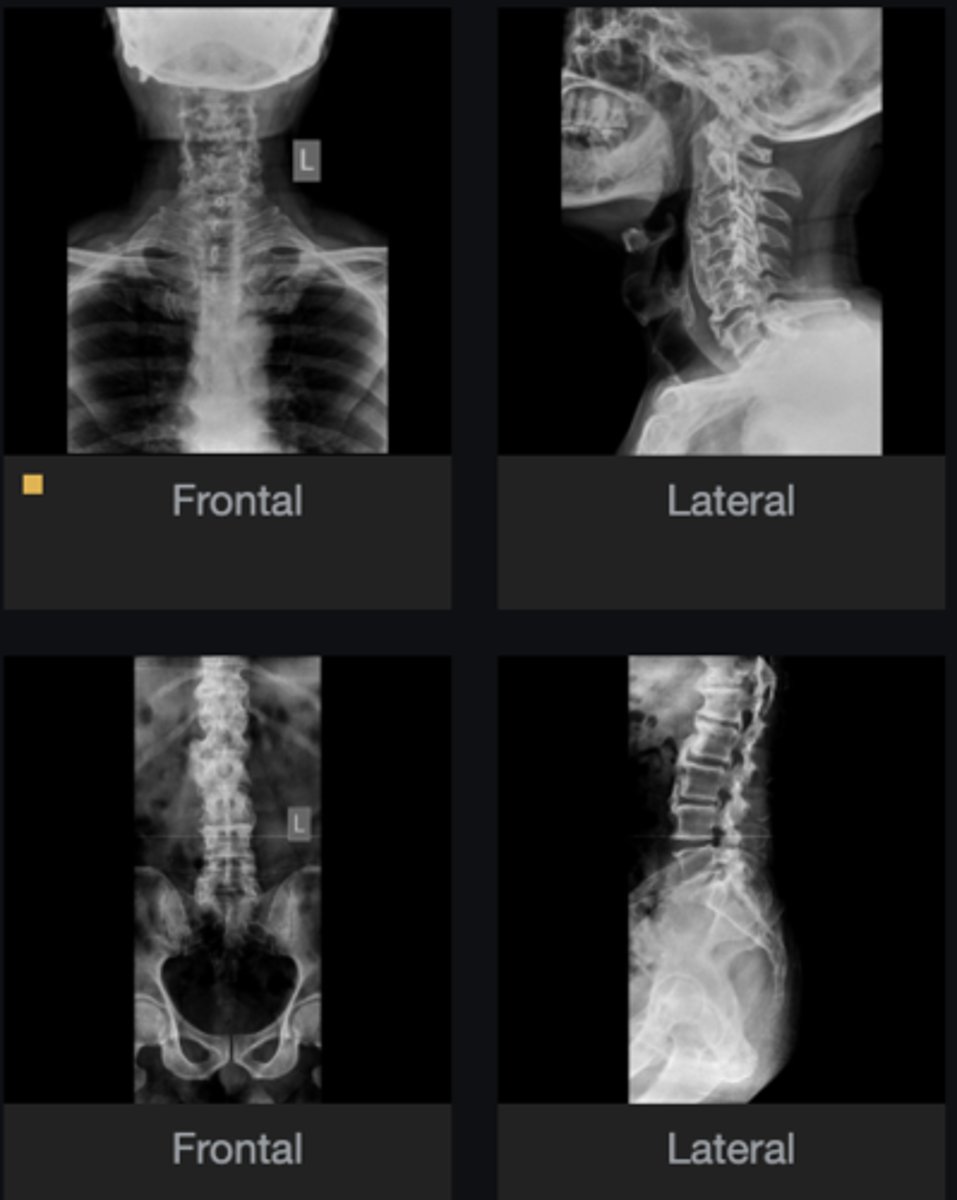

- Calcification of anterior longitudinal ligament

- Intercalary bone

- Preserved disc height across 4 levels

List at least 3 findings

Ossification of the posterior longitudinal ligament (OPLL)

What complication has occurred in the cervical spine?

Diffuse idiopathic skeletal hyperostosis (DISH)

Most likely diagnosis?

Neurosurgeon referral

Next step?

No

Would you adjust this patient?